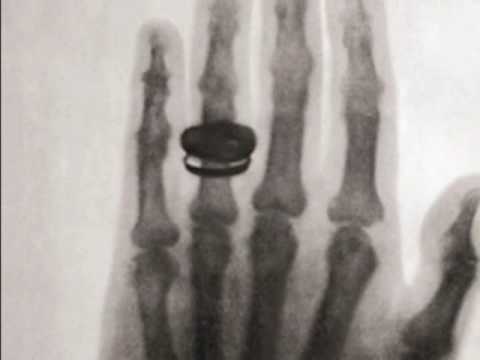

พ.ศ. 2438 (ค.ศ. 1896) - หนังสือพิมพ์ในประเทศออสเตรีย รายงานการค้นพบรังสีชนิดใหม่โดย วิลเฮล์ม คอนราด เรินต์เกน ต่อมาเรียกว่ารังสีเอกซ์

1896 The First X-Ray

Credit: https://www.youtube.com/watch?v=zwJcqCVVEvM